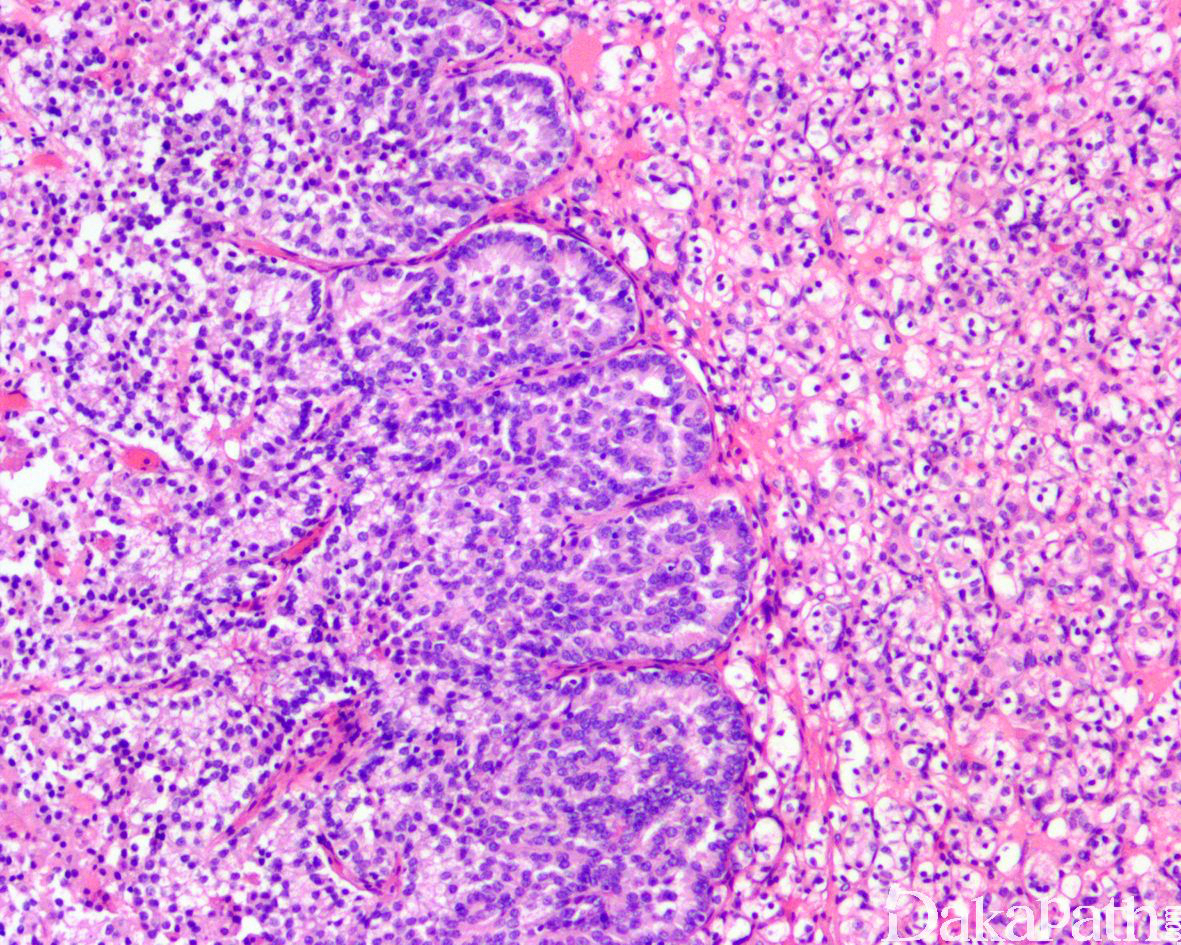

组织学特征不能归类为特定的肾细胞癌类型,该类型包括但不限于:

1)具有两种或两种以上特指类型的肾细胞癌组织形态,伴黏液产生或伴不能识别的上皮细胞类型;

2)低级别或高级别不能分类的嗜酸细胞肿瘤;

常见血管淋巴管浸润及坏死

需要除外转移癌及尿路上皮癌;